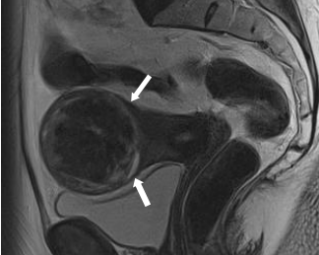

Eine gynäkologische Untersuchung ergänzt durch eine Vaginalsonographie ist in den meisten Fällen ausreichend zur Diagnose beim Uterus myomatosus. Stellt sich aber die Frage einer Abgrenzung zum Leiomyosarkom oder soll im Hinblick auf eine organerhaltende Operation die genaue Anzahl, Lage und Grösse mehrerer Myome bestimmt werden, ist die sonographische Diagnostik meist überfordert. In diesen Fällen, aber auch zur Abgrenzung gegenüber...